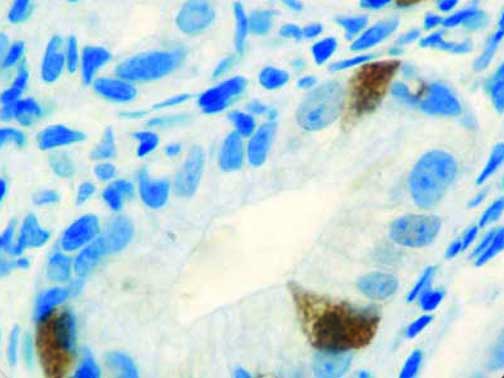

The first cytokines released are interleukin 1β (IL-1β) and tumor necrosis factor-α (TNF-α), which attract a variety of circulating white blood cells (WBCs) to the infection site, including neutrophils, monocytes, macrophages, and natural killer (NK) cells. This response, along with the antipathogenic chemicals released by these cells (i.e., complement), comprise the innate immune response. These cells directly attack the invading pathogen and also release additional cytokines, chief among them interleukin-1 and 6 (IL-6). IL-6 is essential for invoking the adaptive immune response, which calls T-cells, B-cells, and T helper (Th) cells to the infection site. IL-6 also stimulates further recruitment, proliferation and activation of macrophages.